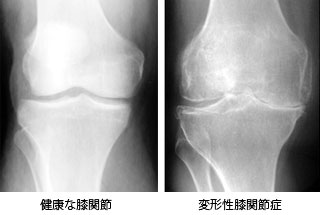

膝や股関節の痛みの原因が、実は違う関節だったという場合があります。 客観的にしっかりと診断をつけて治療することが重要です。 Q 本日は股関節と膝関節についてお話を伺います。 まず、股関節の疾患について教えてください。 A 股関節で一番多いのは 変形性股関節症(へんけいせいこかんせつしょう) です。 股関節は、お椀状の骨盤の中に球状の大腿 股関節痛の改善ストレッチで絶対やってはいけないこと 股関節痛で困っているとき、 「ストレッチをしたら痛みが楽になるのでは」 と考える人は、まあまあ多いんじゃないかな~って思います。 そんな人のためにと、「股関節痛に効くストレッチは、これだ! 」、「このストレッチで股関節痛が劇的改善! 」などと、様々なストレッチ法が多くの 「股関節の痛みの原因は股関節にはない」 一般の人から見ると「???」となりそうな話題ですが、実際にはこんなことはリハビリの現場では日常茶飯事です。 番組では腰痛や膝痛を抱えいてる方の原因は股関節からくるという図式でしたね。 股関節のことならせっかくなので当ブログで

膝の痛みのほかに以下のような特徴や症状が見られる場合、変形性股関節症が発症している 可能性があります。 股関節、お尻、太もも、ひざの上などに痛みがある 股関節の動きが悪く、曲げ伸ばしがしづらい。 または動かせる範囲が狭い 足を引きずって歩く(跛行) 変形性股関節症に伴う症状は、病気が進行するにつれて変わっていきます。 病気の初期は、股